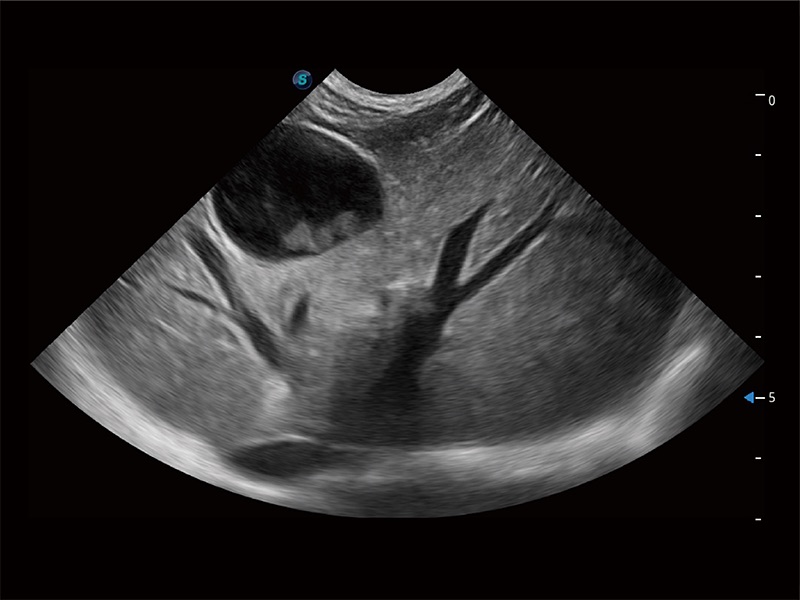

(犬)肝脏

(猫)胆囊

(犬)胎儿主动脉弓立体血流

(犬)四腔心MQA

(犬)肠道

(犬)肾脏显微血流

(犬)胎儿四腔心

(猫)二尖瓣M型

(犬)二腔心血流

优异的基础图像

ProPet 80 全新的动物超声智能软件和丰富的探头群,为动物医生提供了高清晰度和精细分辨率的图像,无论在宠物、马科、畜牧还是实验室动物等应用中都可以轻松应对,为您的日常工作带来满意的体验。